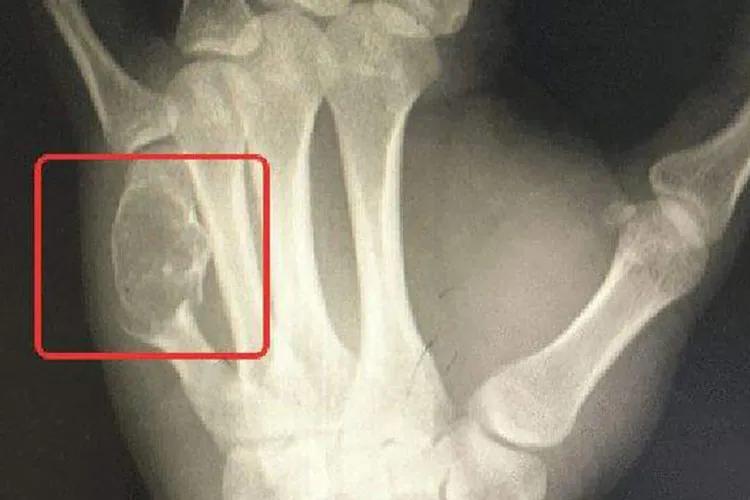

骨癌的早期症状图片

骨癌肿胀图

骨癌肿块图

骨癌骨头变形图

骨癌可通过病史、体格检查及辅助检查来进行诊断。体检检查及X线检查可判断肿瘤部位;CT及MRI检查可显示肿瘤软组织侵犯和髓腔浸润程度;肺CT判断有无肺转移;骨扫描排除骨转移;病理学检查为骨癌确诊依据,通过针吸活检或切开活检进行病理检查,可以明确诊断并进一步确定肿瘤亚型。